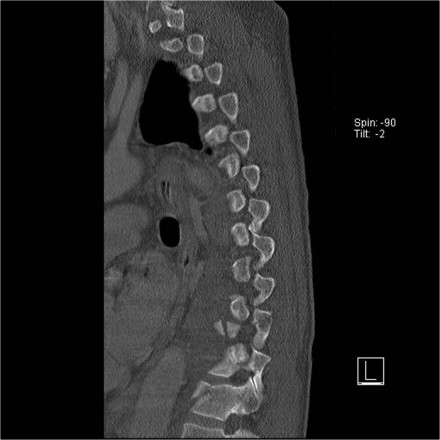

The images are of a patient with a typical bamboo spine as a result of ankylosing spondylitis.

After a fall on his back no fracture was seen on the x-rays.

However the CT shows a thin fracture line through the anterior side of the vertebral body and also through the spinous process.

Look at the images.

What are the findings?

Then scroll to the next images.

The findings are:

- Vertebral bodies show marrow edema as a result of a fracture.

- Torn flaval ligament (yellow arrow).

- Fractures through the posterior elements (red arrows).

The TLICS-score is high, because there is distraction and injury to the PLC.